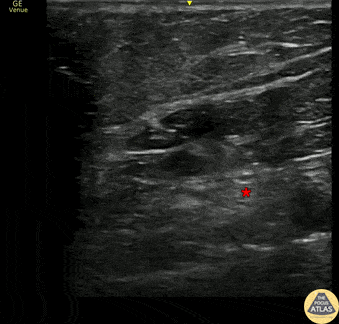

30s F presented with multiple self inflicted lacerations to the leg. To facilitate laceration repair without using a near toxic dose of lidocaine, a popliteal sciatic nerve block was performed. The block is shown here with the needle approaching from the lateral aspect of the popliteal fossa, in plane with the probe, depositing anesthetic next to the popliteal nerve (*). The anesthetic in this clip is outside of Vloka’s sheath, which encompasses the sciatic nerve and its more distal branches, the common peroneal and tibial nerves. Accordingly, onset of anesthesia in this patient was delayed, and so the laceration repair was completed using a combination of local infiltration of anesthetic as well as this nerve block. Dr. Kathleen Joseph, PGY3 Denver Health Residency in Emergency Medicine